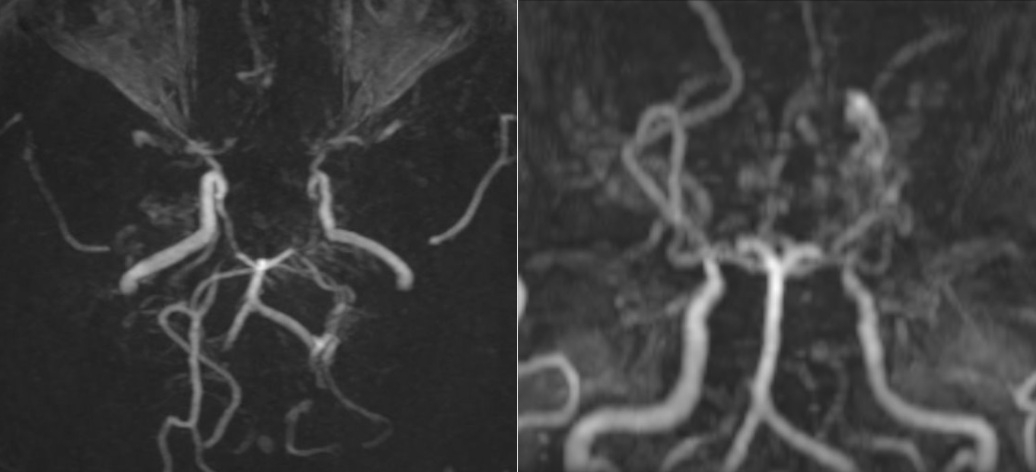

Các mạch máu não của bệnh nhân nhìn như “làn khói thuốc lá” trên phim chụp MRI.

Tại Bệnh viện đa khoa Medlatec, qua thăm khám lâm sàng, bệnh nhân không có dấu hiệu thần kinh khu trú hay tăng áp lực nội sọ. Để làm rõ nguyên nhân, bác sĩ chỉ định chụp cộng hưởng từ (MRI) sọ não. Kết quả MRI cho thấy, hình ảnh tổn thương hẹp tắc động mạch cảnh trong hai bên và các nhánh của đa giác Willis, xung quanh hình thành tuần hoàn bàng hệ với nhiều mạch máu nhỏ bất thường.

Đồng thời, trên chuỗi xung FLAIR, xuất hiện những dải tín hiệu sáng chạy dọc theo rãnh cuộn não, gợi hình ảnh “dây thường xuân” len lỏi trên bề mặt, phản ánh sự gia tăng tuần hoàn bàng hệ màng mềm để bù đắp cho tình trạng thiếu máu não do tắc nhánh mạch não. Bên cạnh đó, bác sĩ cũng phát hiện một hình ảnh tổn thương cũ ở vùng trán trái, là biến chứng của bệnh lý Moyamoya.

Chẩn đoán hình ảnh phát hiện tình trạng hẹp hoặc tắc nghẽn phần cuối của động mạch cảnh trong sọ, rồi lan rộng ra các động mạch não trước, não giữa, não sau; phát hiện mạng lưới mạch máu bất thường ở vùng lân cận của các tổn thương dạng “làn khói thuốc”. Bệnh Moyamoya nếu không được phát hiện và điều trị kịp thời có thể dẫn đến đột quỵ, tàn phế hoặc tử vong.